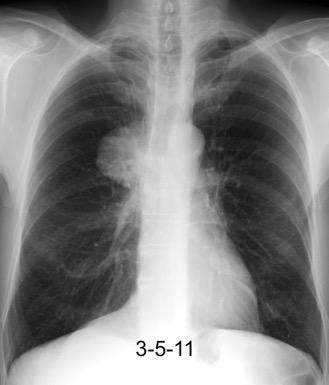

Síndrome de afectación postcardiaca (postcardiac injury)

Post infarto 1-7 % (Dressler)

Trauma cerrado Implantación marcapasos

Cirugía cardiaca. 17-31% (Post.pericardiotomía)

3707 pacientes 29 Derrames (0,78%) > de 25% del hemitórax

Todas menos 2 Izdos.

Angioplastia

By-pass coronario 21-10-03